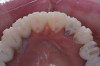

Figure 3  Preoperative view. Note the worn incisal edges and end-on-end occlusal relationship requiring an increase in OVD to restore.

Figure 3